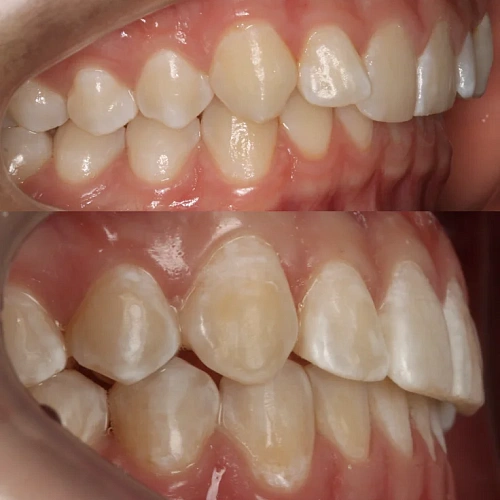

Нарушение соотношения челюстей и неправильное положение зубов — зубные ряды смыкались некорректно, зубы стояли со смещением.

Проблема: В клинику обратился мужчина с жалобами на неправильное положение зубов и смыкание — ряды сходились некорректно, зубы стояли со смещением. При этом было важно, чтобы лечение оставалось незаметным для окружающих, поэтому вариант с брекетами не рассматривался.

Решение: Поставили элайнеры Invisalign на обе челюсти. Лечение заняло 4 года — случай потребовал нескольких этапов коррекции, каждый из которых последовательно приближал зубы к нужному положению. Капы менялись каждые 1–2 недели, контрольные визиты — для отслеживания прогресса и выдачи новых наборов. Зубы встали на место, смыкание пришло в норму. Зафиксировали ретейнеры на обе челюсти, пациент направлен к ортопеду для завершающего этапа.